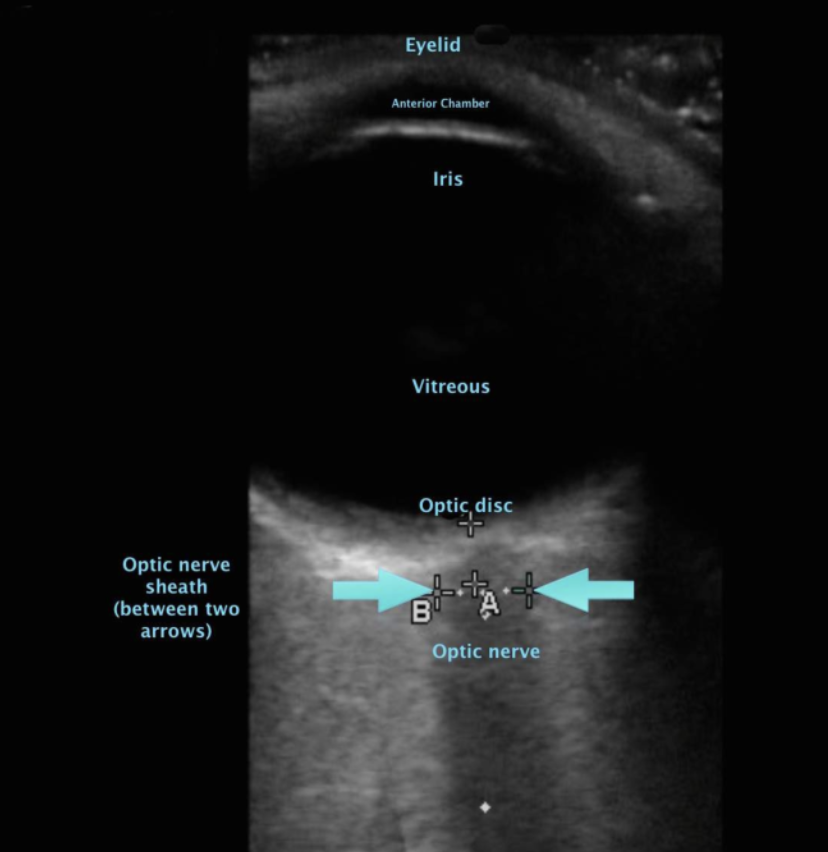

• 眼球エコーにおける視神経鞘(Optic Nerve Sheath Diamter:ONSD)の増大は頭蓋内圧亢進を示唆する可能性がある

Shevlin C. Optic nerve sheath ultrasound for the bedside diagnosis of intracranial hypertension:pitfalls and potential. Critical Care Horizons 2015:1:22-30.より引用

• 眼球後方3mmの位置でONSDを測定する